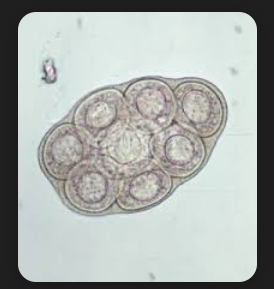

HYEMENELOPIS DIMINUTA OVA W.M